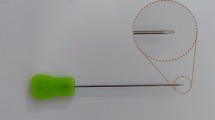

Thread release

After ultrasound visualization of relevant anatomical structures, a spinal needle (20-gauge × 90 mm, TRO-Spinoject, Troge Medical GmbH, Germany) was inserted into the skin approximately 1 cm distal to the A1P and advanced beneath the A1P (Fig. 3, a). Under continuous hydrodissection, the needle was advanced toward the exit point proximal to the proximal border of the A1P and a commercial medical grade stainless steel woven thread, with a high friction coefficient, 22 Gauge (0,6 mm in diameter) and 20 cm in length was passed through the needle (Fig. 3b). Similar to the needle release, about 2–3 ml of saline were injected. The needle was then withdrawn and reinserted above the A1P under hydrodissection, using the same entry and exit holes (Fig. 3c). The thread was then inserted again, creating a loop around the A1P (Figs. 3d, e and 4,Video 3), which was confirmed by control HRUS. After ensuring the correct thread position, the ligament was transected by applying alternating forces to the thread using the thread as a saw (Video 4). The technique was adapted from Guo et al. [19]. To facilitate identification of the thread pathway during subsequent dissection, the thread was soaked with hematoxylin–eosin stain.